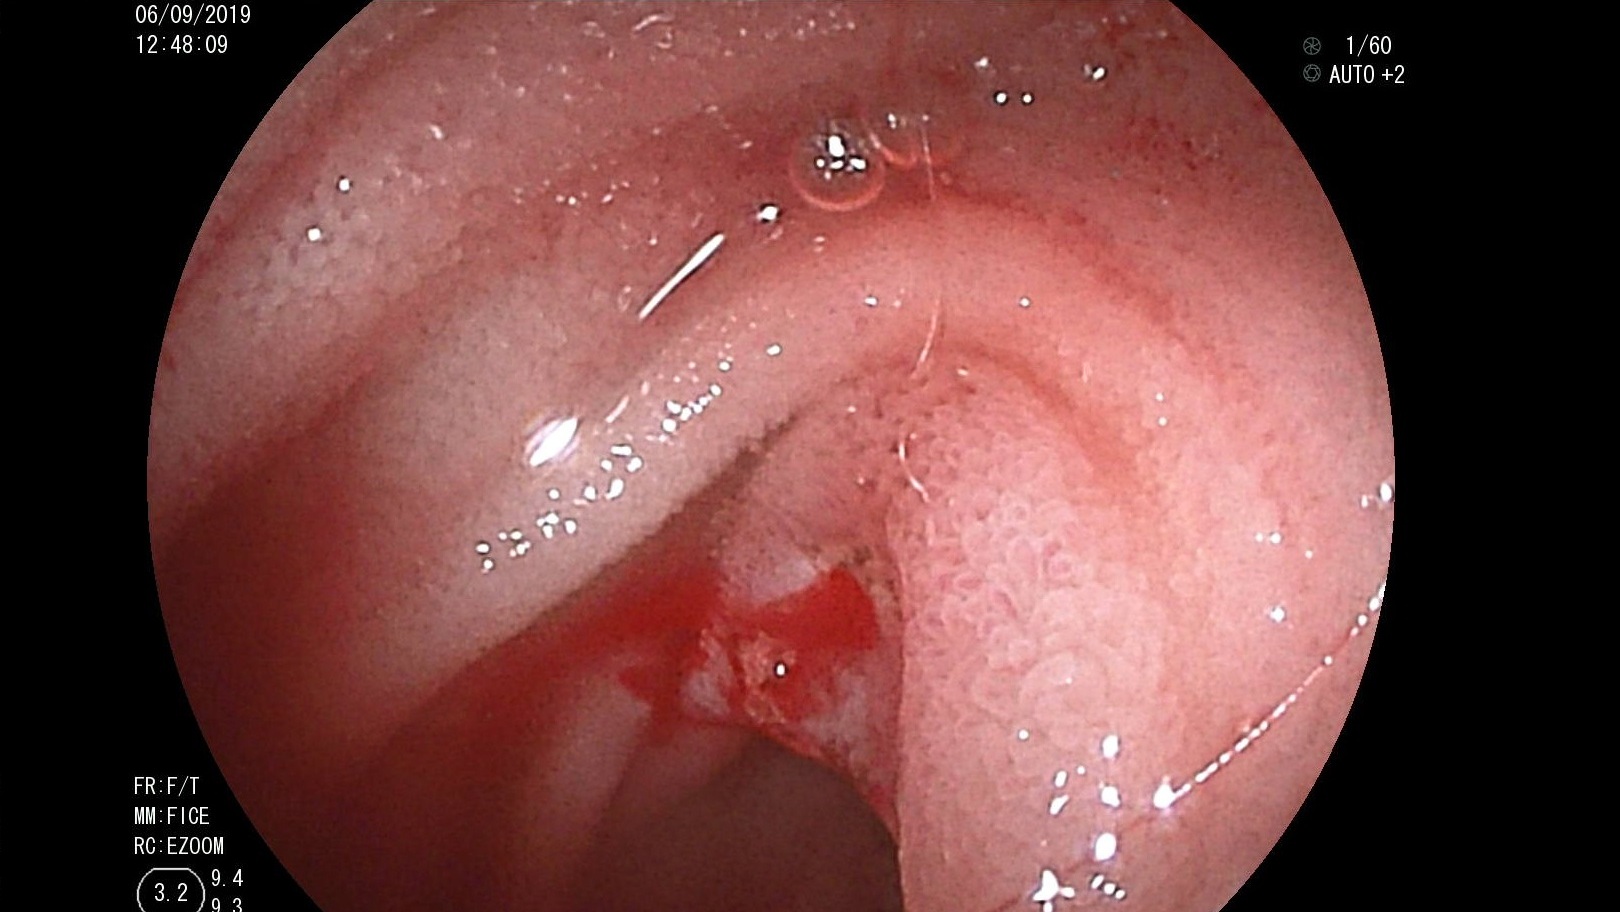

Thông tin Y tế

Cứu sống một trường hợp xuất huyết tiêu hoá nguy kịch từ ruột non bằng nội soi ruột non bóng đôi ở Bệnh viện Trường đại học Y – Dược Huế

Bệnh nhân LTHM, nữ, 31 tuổi, tiền sử suy thận mạn giai đoạn cuối đang chạy thận nhân tạo, được các bệnh viện ở Đà nẵng chuyển ra bệnh viện Trung Ương...